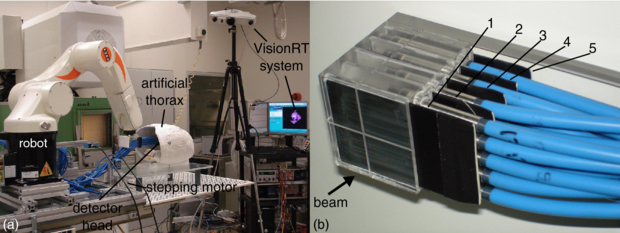

The basis of the artificial thorax is a commercial artificial skeleton (Skelett Bruce—Teng Long Trading GmbH & Co KG, St. Pölten, Austria) which consists of polyvinyl carbonate (PVC). All but the thorax was removed and all metal components used by the manufacturer to connect the plastic bones (screws, wires, rods) were exchanged with plastic. After that the thorax was surrounded by rubber to generate a skin-surface and inter-rib material. This led to a thorax wall thickness of about 1 cm. The artificial thorax is shown in figure 1(a). Rather than using anthropomorphic materials that are equivalent to that of bone/tissue, we chose to use a dedicated lookup table to convert the Hounsfield units (HU) of the CT scan into water-equivalent path lengths (WEPL) for use with particle irradiation (Jaekel et al 2001) as is also carried out for patient treatment planning.

Figure 1. (a) Photograph of the setup at GSI showing also the VisionRT system. The detector head is shown in irradiation position within the artificial thorax. For further illustration, a video attachment can be found online (available from stacks.iop.org/PMB/57/2235/mmedia) showing correlated motion of the target and thorax. (b) Picture of the fully equipped detector head. Four rows of pinpoint ionization chambers with five chambers per row are used for 3D dosimetry within the target volume. In between the rows, in front of the first and behind the last row light-proof film cases are placed (black plates) covering radiographic films for homogeneity measurements.

Standard image2.2. The tumour (detector head)

The tumour is represented by a cube consisting of polymethyl methacrylate (PMMA) which provides slots for 20 pinpoint ionization chambers (PTW PinPoint® model 30 009/30 015—PTW, Freiburg, Germany) and five light proof film cases covering radiographic films (detector head).

Figure 1(b) shows the detector arrangement within the detector head. In beam eye view (BEV) projection, the pinpoints have a lateral distance of 1 cm from each other. The rows are at a distance of 12 mm (compare also figure 3) from each other. The film cases can easily be replaced by non-irradiated ones. Re-equipping of a set of five film cases is doable in less than 10 min in a dark room. The films were developed using a standard development machine (Kodak X-Omat M35—Kodak GmbH, Stuttgart, Germany; Agfa Curix 60—Agfa-Gevaert N.V., Mortsel, Belgium).

A nylon cord which is attached to the sternum is periodically pulled and released by a stepping motor (AS1050—200 full steps per revolution, micro step factor 64—Beckhoff Automation GmbH, Frankfurt, Germany) via a lever arm (PMMA). This pulling results in contraction and deformation of the thorax and, therefore, introduces thorax motion. The stepping motor is placed at the edge of the base plate (PMMA) to avoid having metal in the scanning field of the CT (figure 1(a)).